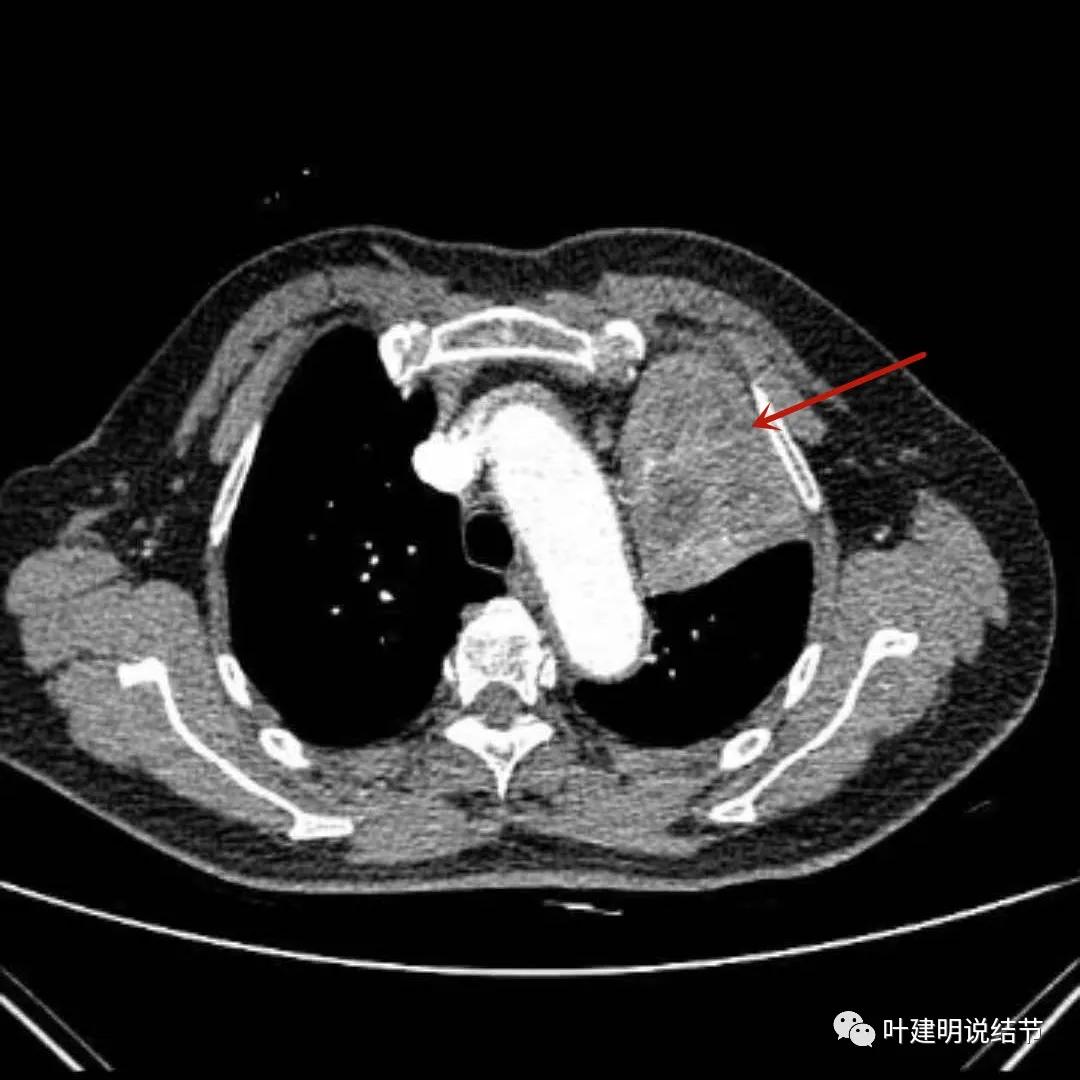

左上肺块影

上图示左上肺肿块,边缘部分应该考虑是不张的肺组织,但黄色箭头所指处是肿瘤内部的坏死区